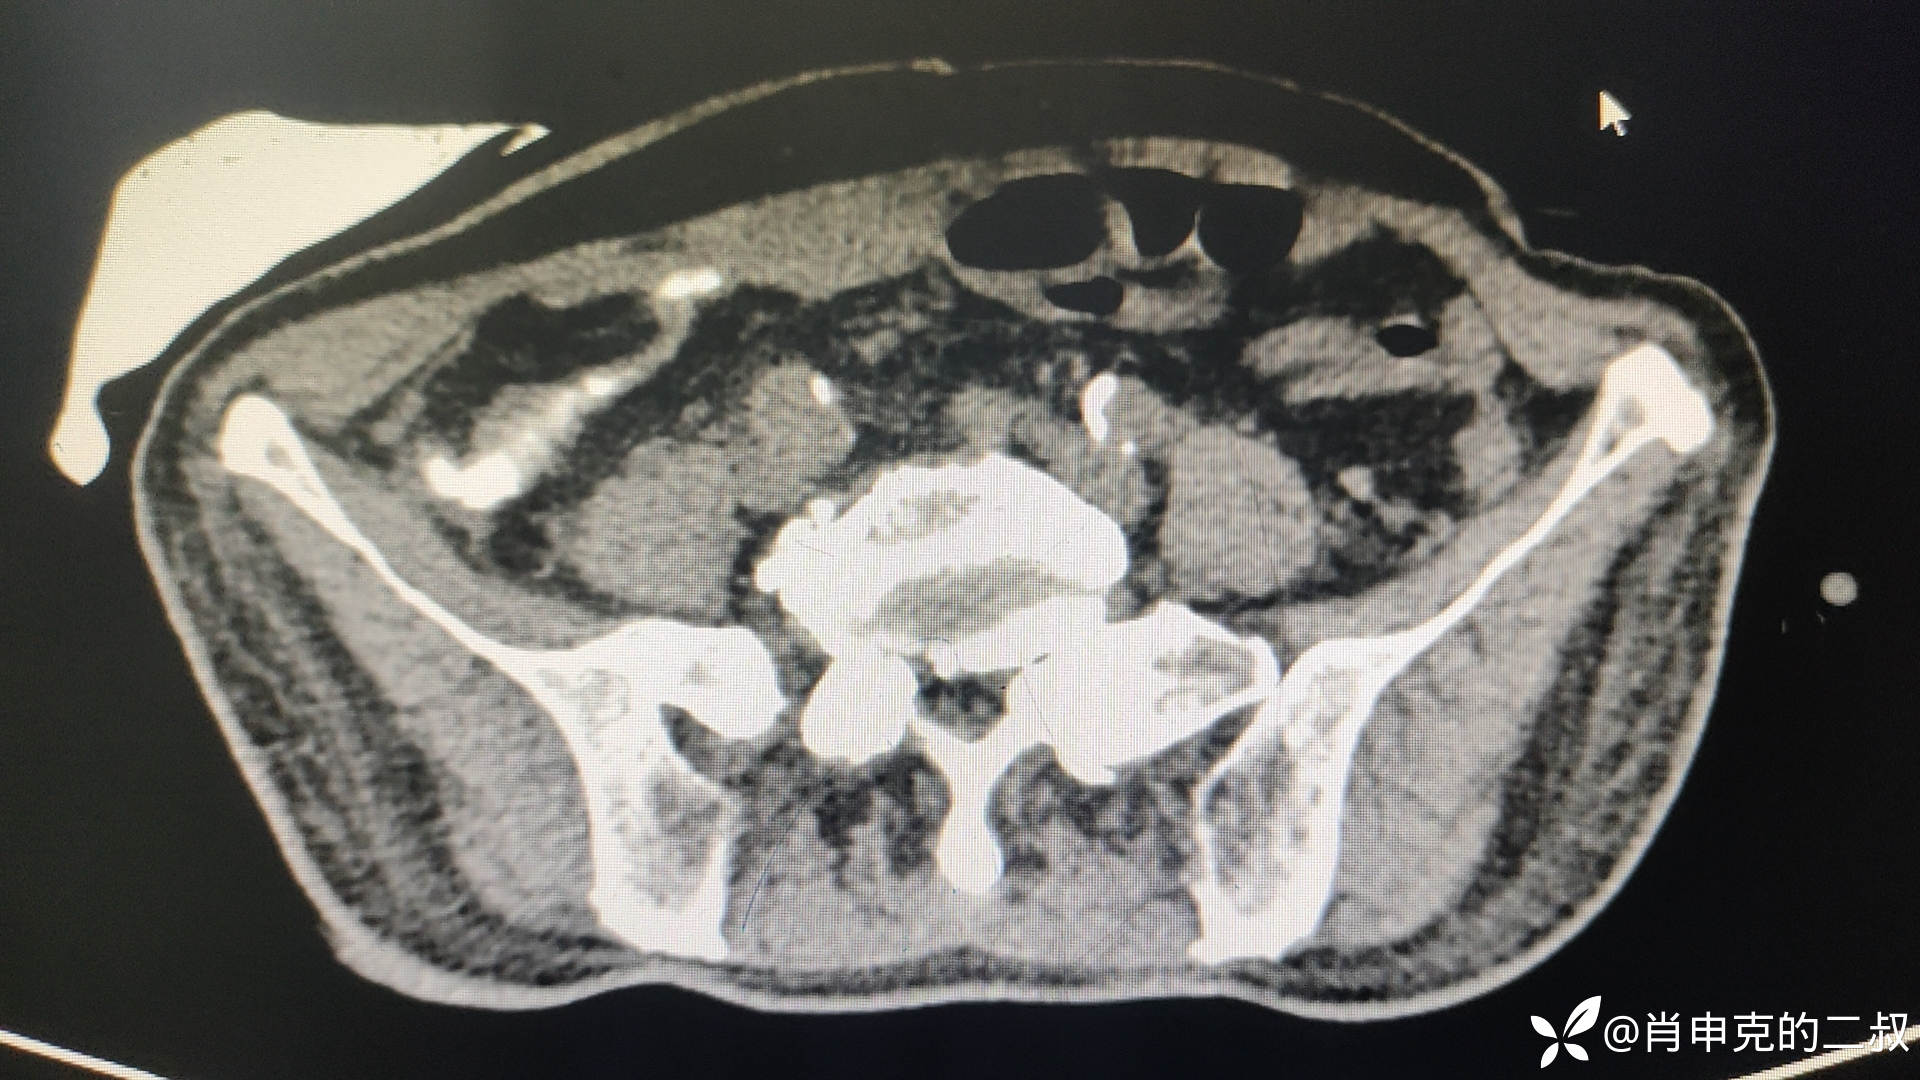

入院后急诊行腹部CT检查:可见结肠、直肠扩张明显。

肠梗阻管治疗第3日,复查腹部CT,并无明确好转。

此时患者,,复查CT:心包积液、胸腔积液、肺部感染、肺不张。。腹部CT反而未见特殊异常。。。